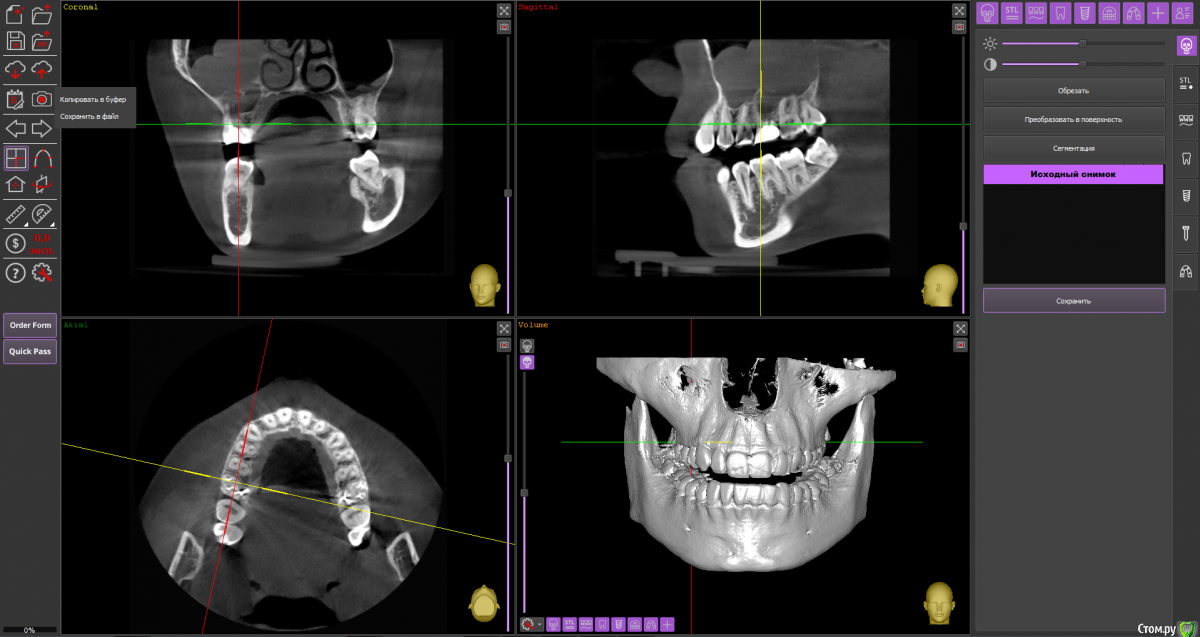

Ольга Вовк Опубликовано 10 февраля, 2021 Поделиться Опубликовано 10 февраля, 2021 Добрый день! Очень прошу помочь по таким вопросам:1. Верхняя шестерка справа - там киста перешедшая в гайморову пазуху (узнала это 4 месяца назад). Зуб ныл 2 года назад, тогда врач просто прописала Аугментин. Все прошло, но опять начал поднывать неделю назад (сейчас опять прошло). Была на консультации, сказали вырывать и прочищать пазуху нужно сейчас, и по приезду уже дальше разбираться. Как лучше быть, если я через неделю уезжаю на 4.5 месяца в страну, где никак не смогу продолжить лечение, а значит ставлю на паузу все на этот период.1. Удалить зуб сейчас, чтоб он зажил и через 4.5 месяца приехав сделать синус лифтинг и ставить имплант, или же ждать это время не удаляя зуб? 2. Не разрушится ли если сейчас не вырвать полностью костная ткань? 3. Можно ли не ставить имлпант, а сдвинуть 7 и 8 зуб к 5ому? Также вопрос по верхней шестерке слева - можно ли ее перелечить под микроскопом, или нужно делать резекцию? Разные врачи сделали разные выводы по нему Ссылка на архив файлов панорамного КТ - http://fayloobmennik.cloud/7414975 Спасибо вам, очень надеюсь на совет Ссылка на комментарий

wladdX Опубликовано 10 февраля, 2021 Поделиться Опубликовано 10 февраля, 2021 (изменено) Зуб 16, мне кажется, лучше удалить до отъезда. Насчёт ортодонтического перемещения 8-го и 7-го на место 6-го, необходимо с ортодонтом очно пообщаться, но на мой взгляд, хирургическое лечение будет более предсказуемым.Зуб 26 может оказаться непростым для эндодонтиста, но если доктор берётся и Вы ему доверяете, то начать стоит с повторного эндодонтического лечения с увеличением. Изменено 10 февраля, 2021 пользователем wladdX 2 Ссылка на комментарий

Ольга Вовк Опубликовано 10 февраля, 2021 Автор Поделиться Опубликовано 10 февраля, 2021 16_1.png 16_2.png 16_3.png 26_1.png 26_2.png 26_3.png 26_4.png Зуб 16, мне кажется, лучше удалить до отъезда. Насчёт ортодонтического перемещения 8-го и 7-го на место 6-го, необходимо с ортодонтом очно пообщаться, но на мой взгляд, хирургическое лечение будет более предсказуемым.Зуб 26 может оказаться непростым для эндодонтиста, но если доктор берётся и Вы ему доверяете, то начать стоит с повторного эндодонтического лечения с увеличением.Спасибо вам огромное! Я так понимаю, что если не удалить сейчас, то тогда к приезду (3 июля) уже совсем костной ткани не останется? Просто если сейчас удалить и будут осложнения, или соустье в гайморову, то я уеду и там не знаю что буду делать в такой ситуации(( Ссылка на комментарий